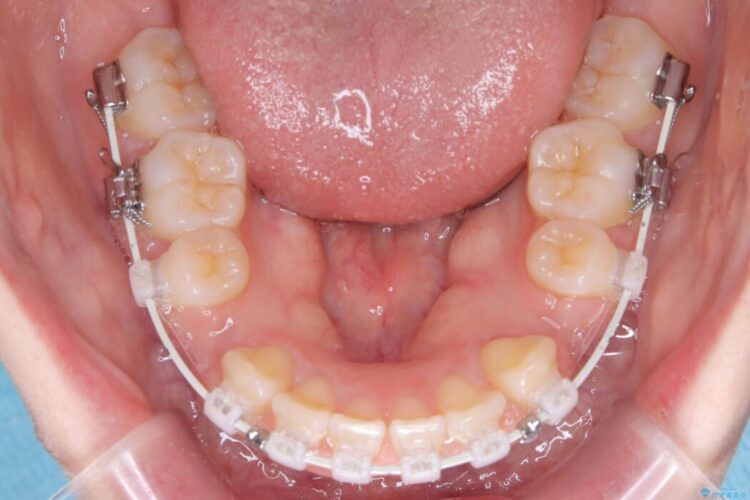

- 矯正装置:ワイヤー(審美装置)

この傾斜を根本から正し、前歯を十分に後方へ下げるスペースを確保するため、上下左右の4番を抜歯し、目立ちにくい審美ワイヤー装置にて治療を行うこととしました。

抜歯で得たスペースを活用し、大きく傾いた前歯の角度を修正しながら、ゆっくりと後方へ移動させていきました。